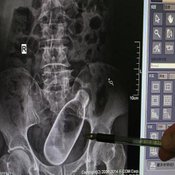

อย่างไรก็ตาม ทางแพทย์ได้เอ็กเรย์ช่องท้องและช่วยกันรักษาโดยนำขวดออกมาได้สำเร็จ พร้อมกันนี้ทางเจ้าหน้าที่ของโรงพยาบาลได้นำภาพเอ็กเรย์ของชายคิดพิเรนทร์คนนี้ออกมาเผยแพร่เพื่อเป็นอุทาหรณ์ให้กับบุคคลทั่วไป จะได้ไม่คิดรักษาตัวเองแบบพิเรนทร์เช่นนี้อีก หรือ ถ้าจะยัดขวดเข้าทวารเพื่อจุดประสงค์อื่น ก็ควรคิดไตร่ตรองให้ดี มิเช่นนั้นอาจจะเจ็บปวดทรมานเหมือนชายชาวจีนคนนี้ก็เป็นได้